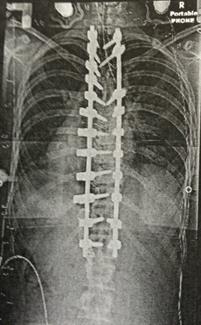

|   As the curve worsened with time, Martinez underwent surgery in which two metal rods and 22 screws were inserted into her back.      |

On June 9, 2015, a couple months before her senior year and the family’s move from Florida to Illinois for Jody to begin working for the Illini, 17-year-old Hannah underwent posterior spinal fusion surgery in St. Louis. Two metal rods and 22 screws were inserted in her back, and a hump on her right shoulder blade was fixed.